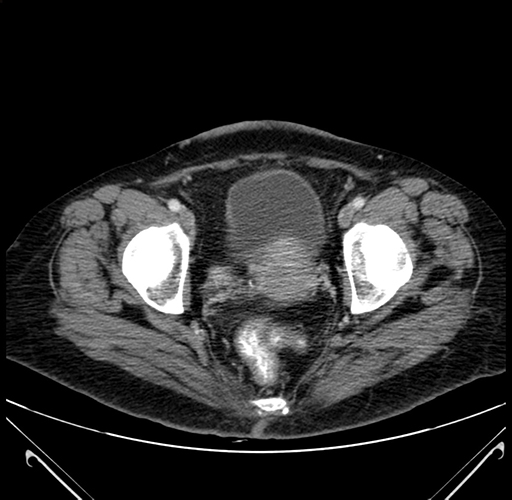

Axial Venous

Coronal Venous